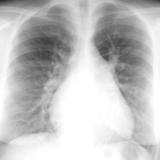

ASD 1 PA&Lat

Date: 03/17/2004

Views: 3067